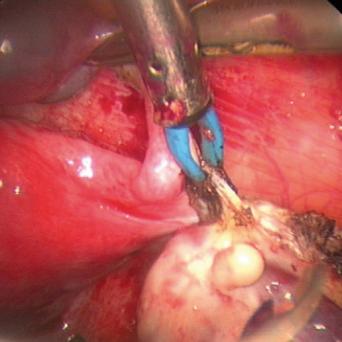

- Particularités de la chirurgie oncologique chez le sujet âgé